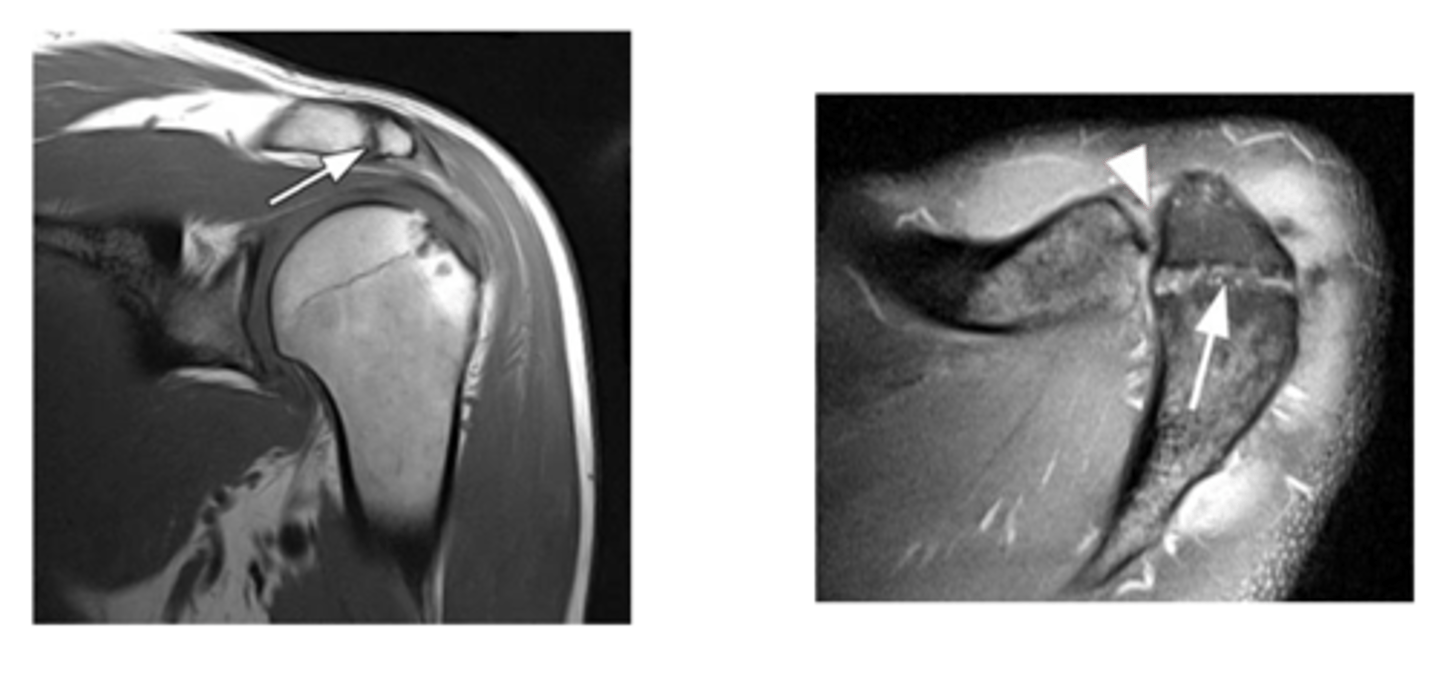

Left image: bursal-sided tear w/ SOME fibers still intact

RIght image: bursal sided AND intrasubstance tears

NOTE: our concern is these partial tears will progress to full tears

What are these images depicting w/ the rotator cuff? What is our concern?